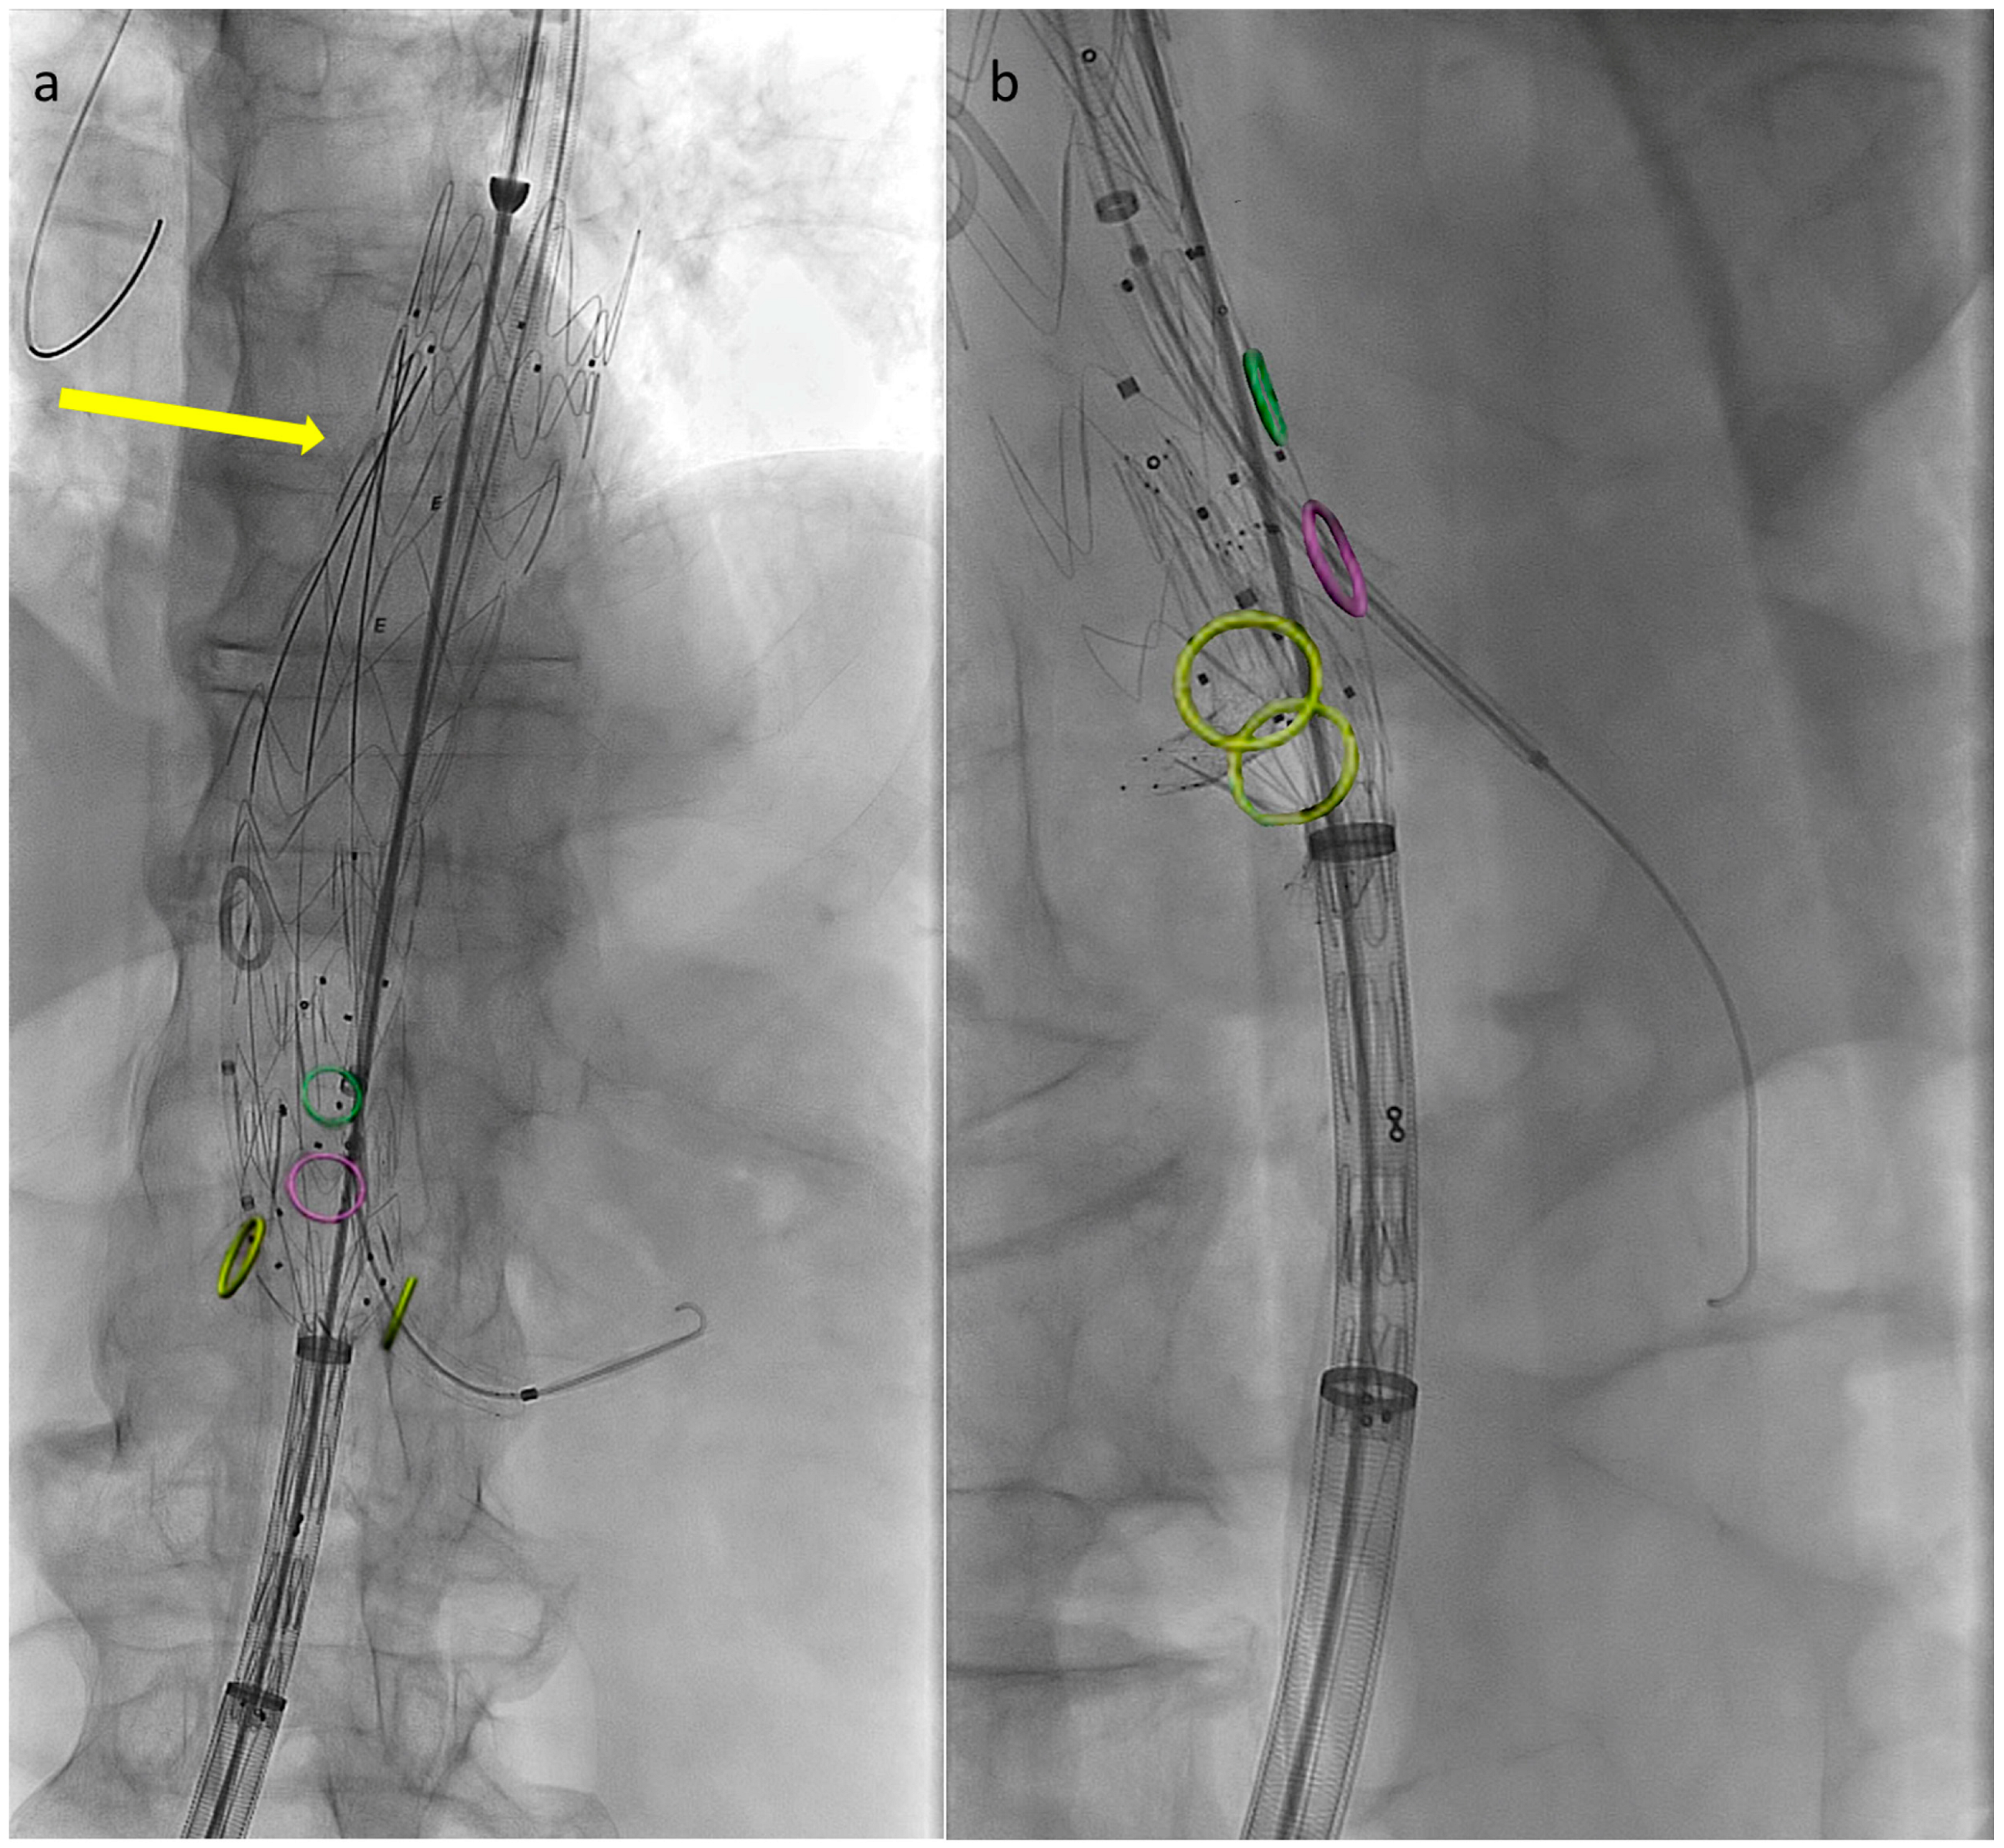

Preventing the distal end of the graft from fully expanding simplifies visceral vessel cannulation maneuvers and bridging component advancement, especially when dealing with restricted lumina (Figure 2). This aspect is even more critical when using an E-nside graft compared to outer-branched devices, given that while the middle portion of the endoprosthesis measures 24 mm in diameter, its distal segment re-expands to 26 or 30 mm with a reverse tapering. The partial deployment approach prevents this distal segment from filling up the inner aortic lumen at the renal artery ostia, a condition dependent on the graft deployment height, potentially leading to target vessel occlusion.

Figure 2. Angiographic images from a case performed using the described technique. Circles indicate visceral vessels origin (positioned using fusion technology). By maintaining the distal endograft constrained into the delivery system the available space for cannulation and bridging components advancement increases. In panel (a) the left renal bridging stent has just been released, the arrow is pointing at the three remining pre-positioned 0.018″ pre-cannulated guidewires. In panel (b) the superior mesenteric artery bridging stent is correctly positioned and ready to be deployed.